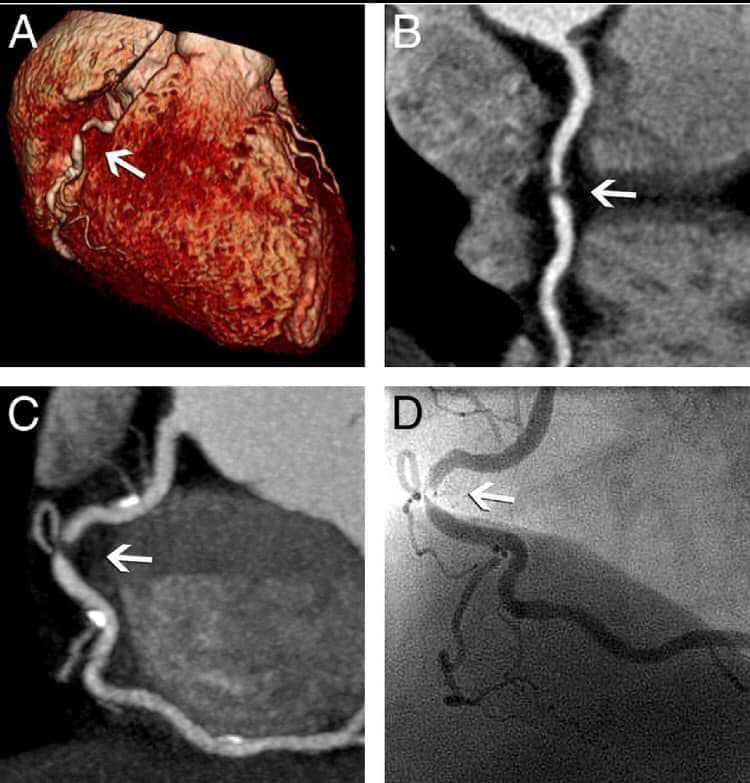

١- الألم الصدري عند الجهد او ما يعرف بالخناق الصدري المستقر على الإجهاد وهو الم يصيب المريض عند القيام بمجهود جسدي معين كمشي حوالي مئتي متر مثلا او صعود ثلاث طوابق او حمل ثقل معين. ويكون هذا الألم بشكل الم في اعلى الصدر والعنق والفك واحيانا في البلعوم والرقبة والكتف الأيسر ويمتد احيانا حتى الذراع الأيسر . وستمر هذا الالم لمدة ٣ او ٤ دقائق على ان يزول نهائيا بعد ذلك . ويحصل كل مرة على ذات مستوى الإجهاد ويتنهي مع توقف الإجهاد ليعود ويظهر مع مع معاودة الجهد ولذات المسافة او الجهد الذي قام به المريض ولذلك نقول عنه انه مستقر لأنه يظهر عند القيام ب ذات الجهد . وهو غالبا ما يكون ناتج عن إنسداد شريان واحد من الشرايين التاجية للقلب ونشخصه بسهولة عبر الوصف والفحص السريري وتخطيط القلب العادي EKG الذي قد يظهر بعض العلامات او عن طريق إجراء فحص الإجهاد: Stress test حيث تظهر ذات علامات الألم مع الركض السريع على سجادة فحص الجهد او على الدراجة الهوائية التي نستعملها من اجل ذلك. وعند إجراء التمييل او القسطرة Coronarograpgy يظهر ان هناك إنسداد واحد او إصابات على شريان واحد من الشرايين التاجية للقلب وعادة ما تكون هذه الإنسدات مهمة وتتراوح بين ٧٠ و ٩٠ او ٩٥ بالمئة ولكنها قطعا لا تكون إنسدادات كاملة اي مئة بالمئة . ومن الممكن في معظم الاحول علاجه بواسطة عملية التوسيع بالبالون والروسور وبعد ذلك تزول كل هذه العلامات او الأعراض ولكن المريض يجب ان يتناول بعدها بعض الادوية التي سنذكرها لاحقا. وطبعا عليه ايضا مراقبة عوامل الخطورة مثل إيقاف التدخين ومراقبة الدهنيات في الدم ومرض السكري وارتفاع الضغط وعلاج كل هذه الامراض بأدويتها المناسبة والقيام بتمارين رياضية شبه يومية او لثلاث مرات في الاسبوع.